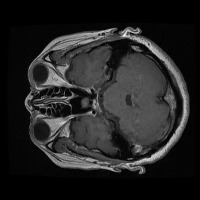

tumor otak Computer Vision Project

Medical Diagnostics: This model can be used for assisting healthcare professionals in diagnosing brain tumors by classifying them into glioma, pituitary, or meningioma, which can save time and lead to early and accurate disease diagnosis.

Health Monitoring Software: It can be implemented in health and wellness apps to monitor a patient's MRI scans regularly, thus providing an early warning system for possible tumor growth.

Training medical students and resident doctors: The model can be used as a training tool for medical students and resident doctors to better understand and identify different types of brain tumors from MRI images.

Research Studies: It may be used by scientists and researchers for creating more focused and comprehensive studies on brain tumors, contributing to advancements in the respective field of study.